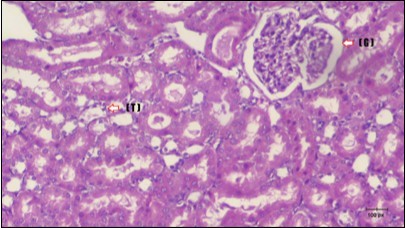

Kidney Histopathological Observations

Kidney sections of diabetic rats showed an increase in mesangial cell and matrix of glomeruli with increase in glycogen deposition and hyalinization of arterioles with thickened basement membranes of proximal and distal convoluted tubules. These changes will lead to progressive reduction in the filtration surface of the glomeruli 35. Histological examination of the kidney of the control rats showed normal structure of renal glomerular. The proximal and distal tubules were lined with normal epithelium (Figure 13). The diabetic rats showed tubular casts, inflammatory cellular infiltration and glomerular atrophy (Figure 14). Kidney of rats in groups (3 and 4) showed some glomeruli return to be normal (G). Focal tubules casts (T) in Fenugreek group and some normal tubules in the Glimepiride group with no inflammatory cellular infiltrate in both groups (Figure 15 and Figure 16). However, kidney of rats in group (5) showed normal glomerular (G), normal tubules (T) with no tubular casts (Figure 17).

Figure 15.Photomicrogragh of kidney section of treated rat with Fenugreek showing improvement of Bowman,s capsules with normal glomerular (arrow) and nearly return of distal tubules (dashed –arrow) and proximal tubules (star) (H&E) (40xX).

Figure 16.Photomicrogragh of kidney section of treated rat with Glimepiride showing improvement of Bowman,s capsules and partial improvement of glomerulir (arrow) and completely return of distal tubules and proximal tubules to the normal shape with wide urinary space. (H&E) (40X).

Figure 17.Photomicrogragh of kidney section of treated rat with both Fenugreek and Glimepiride showing improved cortical tissue with most of both Bowman,s capsules (arrow) and proximal tubules (dash-arrow) with nearly normal structure .Note distal tubules still suffering (star). (H&E) (40X).